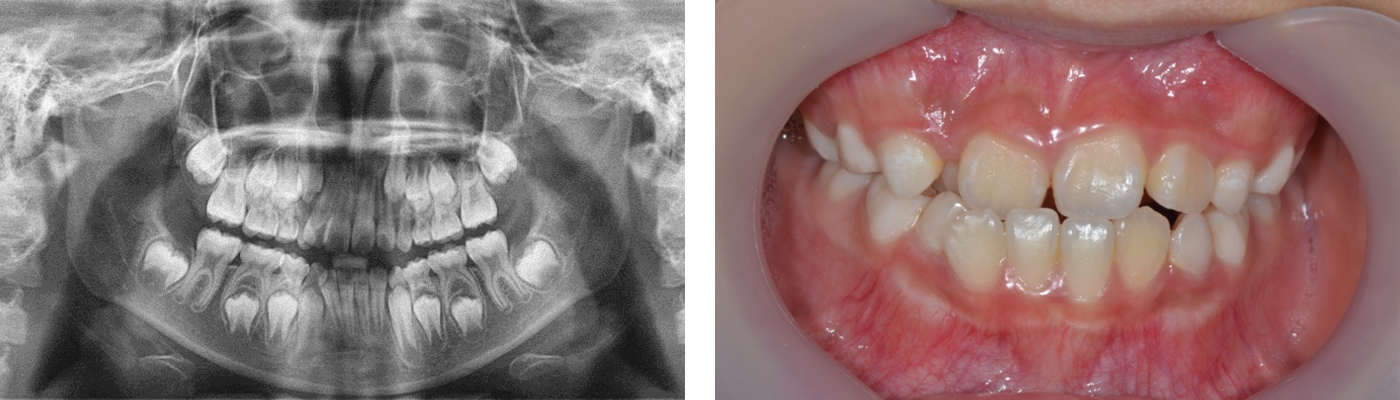

- 초진

- 유치 영구치 혼합 치열기의 상악골 열성장으로 인한 반대교합 소아교정

- 치료 중

- 악궁 확장 장치를 사용한 비발치 교정

- 치료 후

- 교정 10년후에도 유지되고 있는 환자